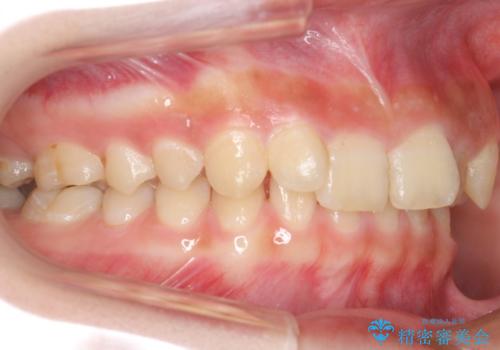

前歯のがたつき 過蓋咬合

今回は上の前歯が内側に傾いている症状があり(Angle Ⅱ級2類)、その修正に時間がかかっています。

奥歯のかみ合わせが、歯と歯が向かい合わせになっておりまた、歯ぎしりも多い方で装置の脱離も頻繁にありました。

ワイヤー矯正ではやや難しい症例でした。